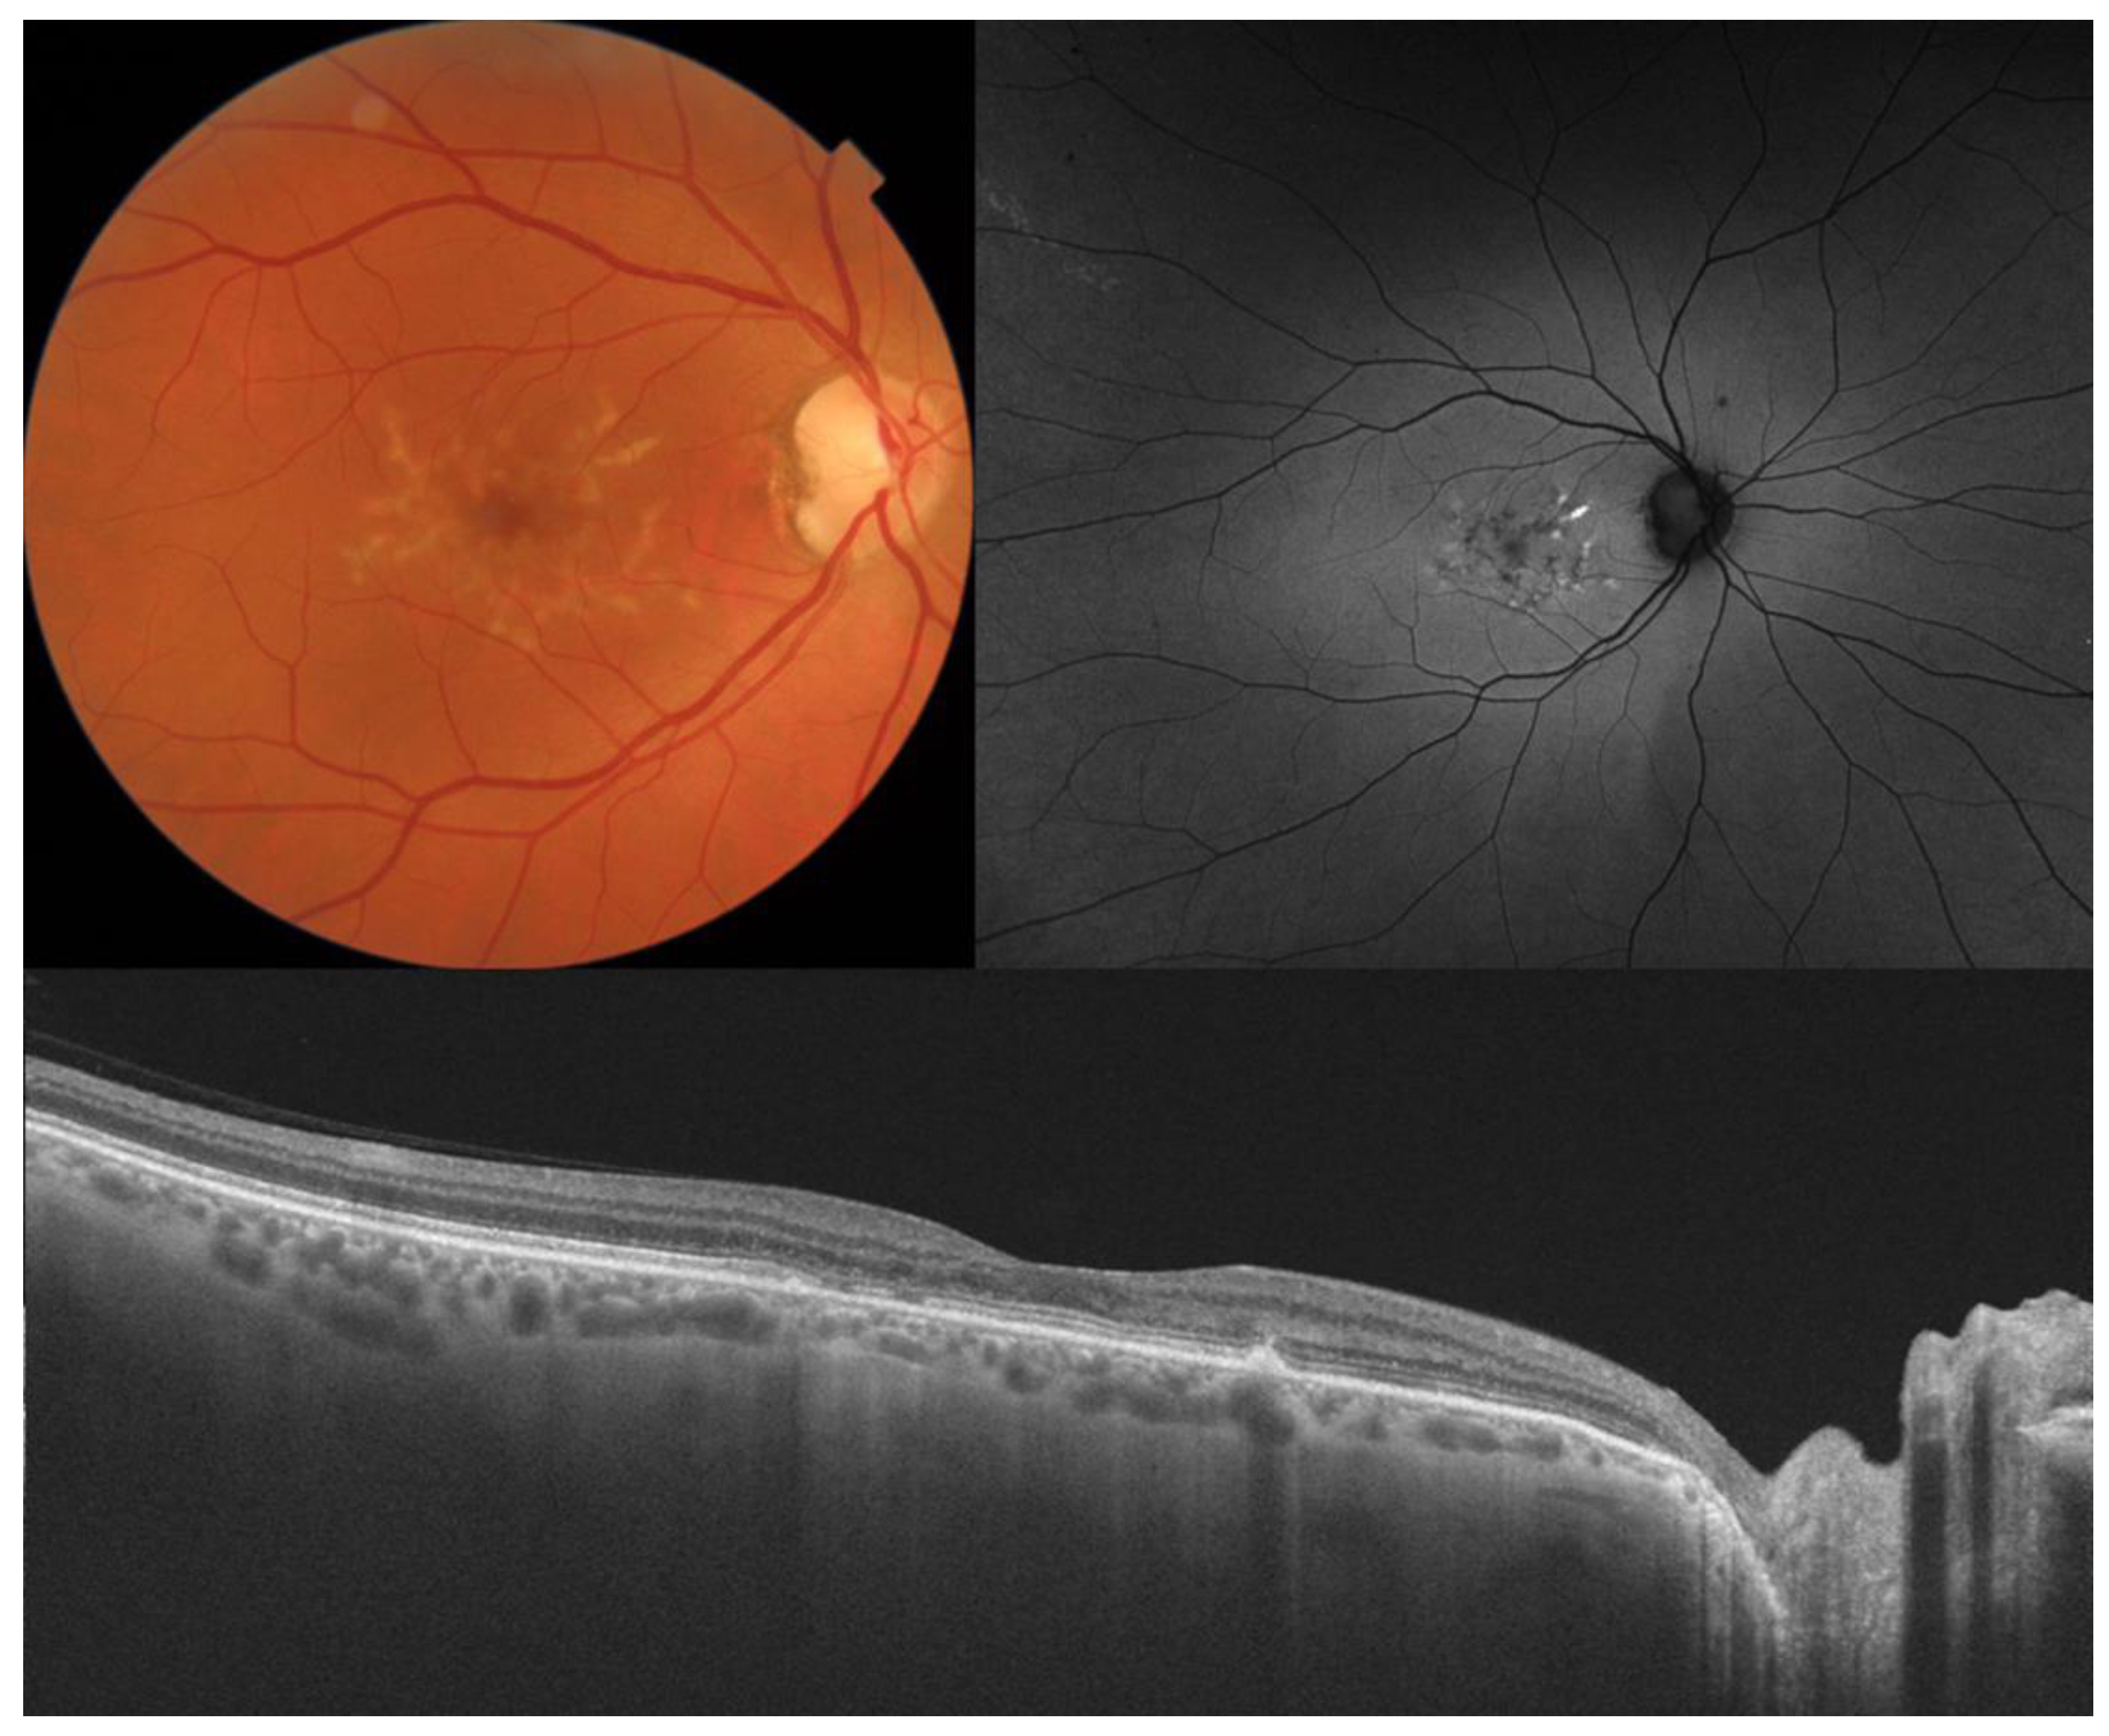

3. Best Vitelliform Macular Dystrophy

| Best vitelliform macular dystrophy |

|